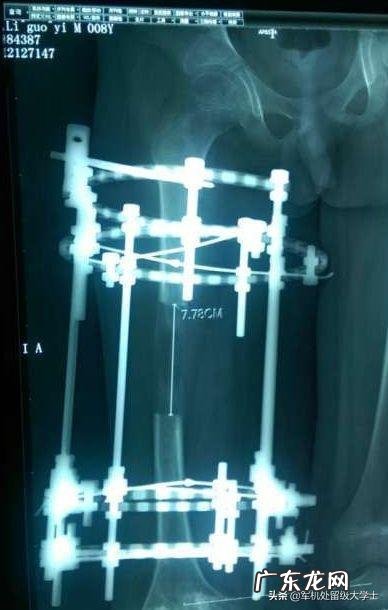

断骨增高,是迄今为止,唯一真正可以增长身高的治疗方法 。这种手术来源于美国,20世纪70年代就有 。通常,做了这种手术的人,可以在一年之内长高5~10公分 。但是,这种方法很不安全,它的风险非常大 。断骨增高的致残疾率,高达10%,每十个人做这种断骨手术,就有一个人残疾 。而且这样的手术导致的残疾,不是一般的残疾,而是重度残疾 。你想想看,硬生生的用工具把你的双腿腿骨切断开来,一旦发生了医疗事故,但不是小事故,你会终身残疾 。到时候,年后悔也来不及了 。有鉴于断骨增高手术的高风险性,卫生部已经下令,严格禁止医院再做这样的增高手术 。除非是可以证明用于残疾整形才可以 。

但很多医生为了效果,两个月增高10厘米,造成了许多病人毛细血管的集体断裂,面临截肢的危险 。

其实,这个术适宜于那些本身骨折的患者,但是没问题只是想增高的话,面临的风险未免太多 。

断骨增高又叫牵张成骨术,是60年代苏联学者提出来的,用于矫形外科足科手术,以及口腔颌面外科修理骨骼畸形 。它最初被用来处理像腿不一样长等问题,但自20世纪80年代以来,最常用于处理以下问题:矮小、微颌症(下巴太小,会引起健康问题)、颅额发育不良、颅缝早闭,以及气道阻塞由以下原因引起的婴儿舌下垂(舌头凹进口腔太远) 。